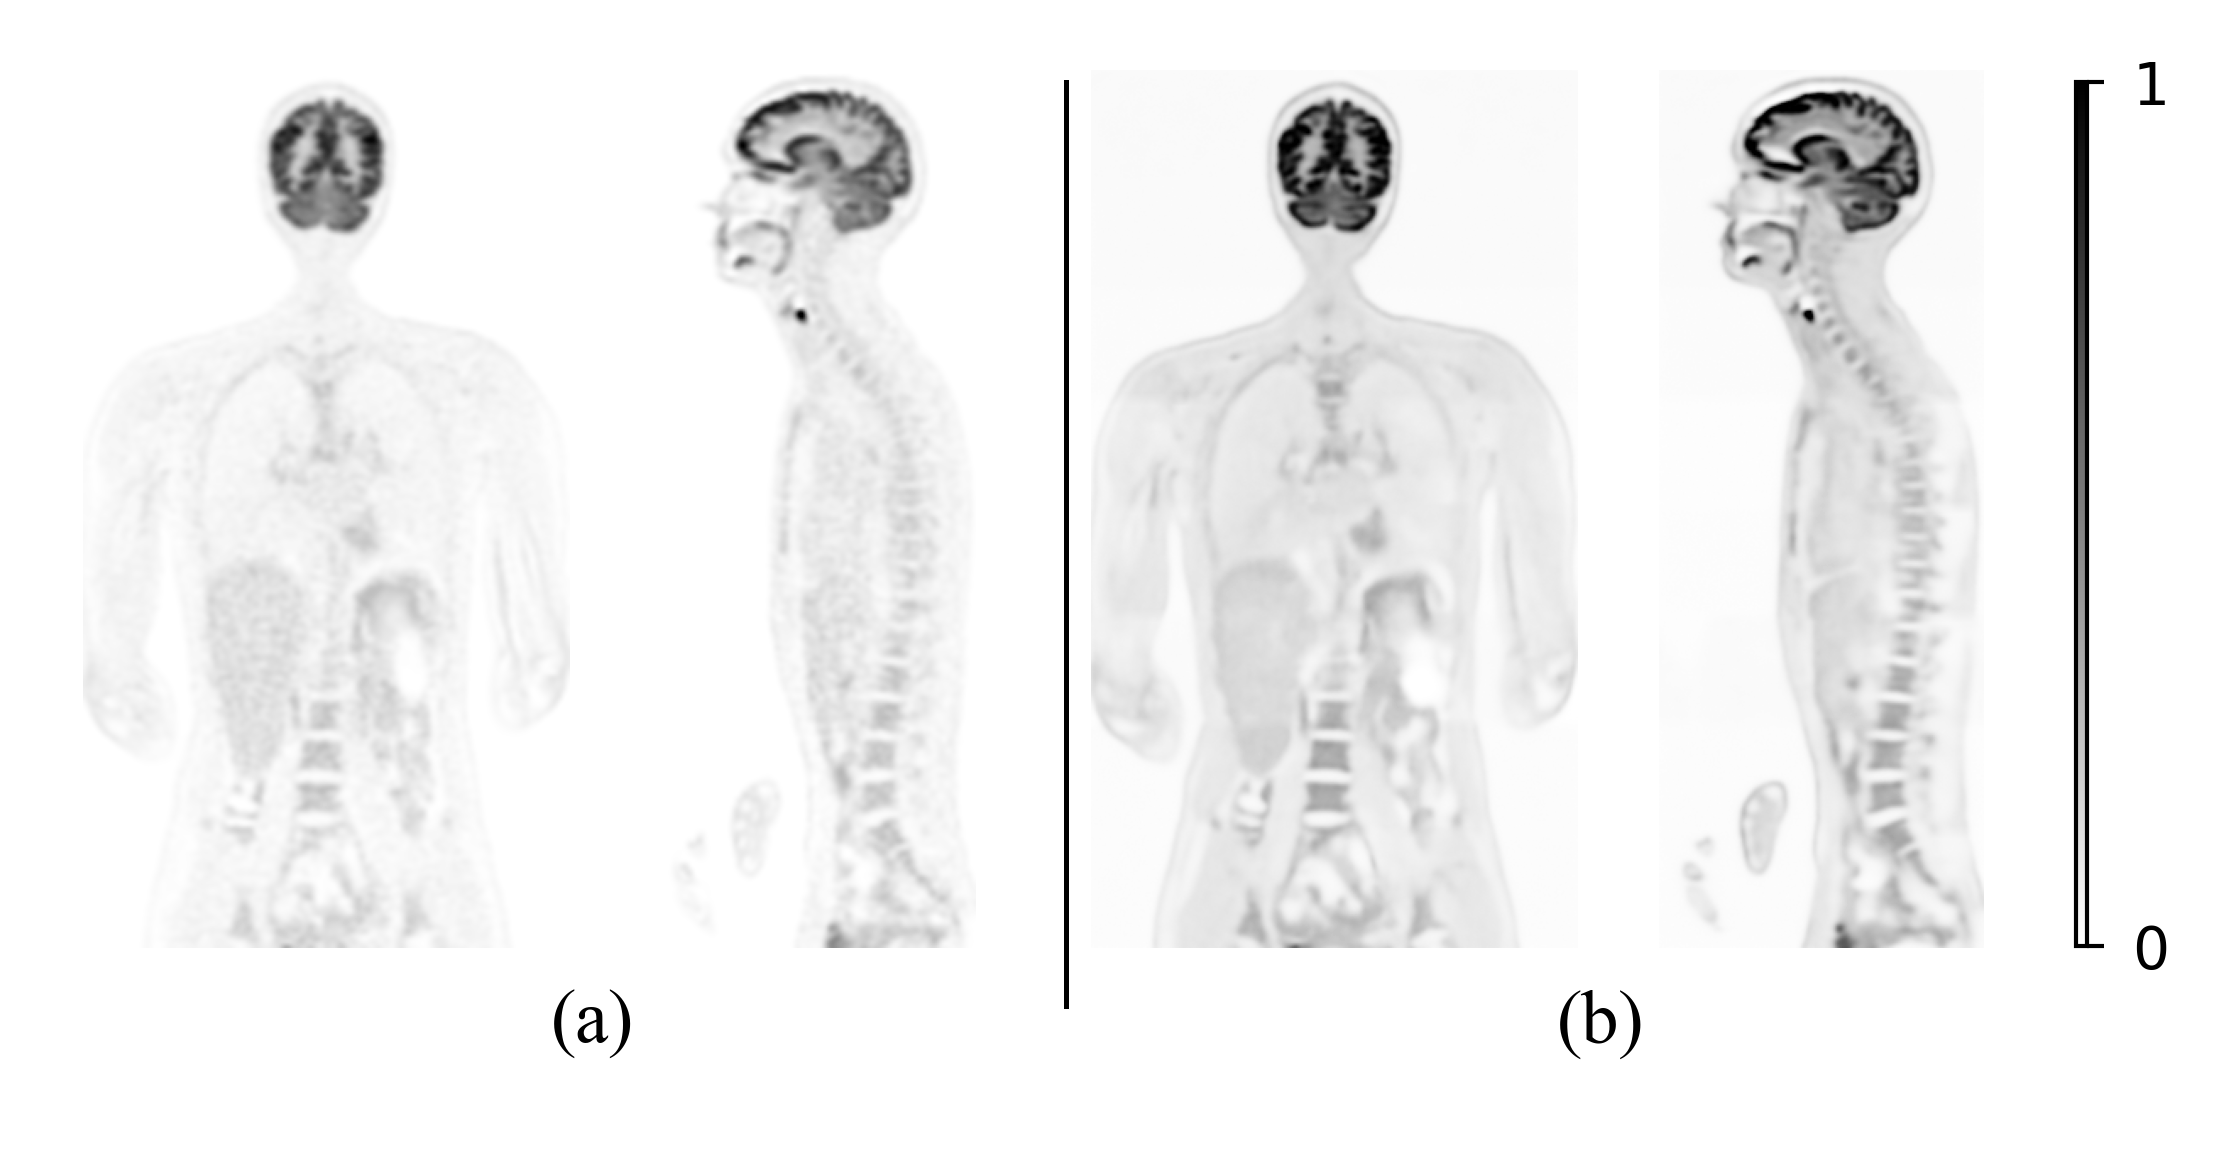

Obtaining a well-trained score function is challenging due to the limited availability of high-quality dynamic PET datasets. To overcome this limitation, we propose to utilize the score function trained on total-body static PET images. The preliminary results in our conference paper [huang2025patlak] are based on this idea and rely on the inference step as described in equation (18). Fig. 1 compares the coronal and sagittal views of Patlak slope images reconstructed using Gaussian filtering and the proposed inference steps as described in equation (18). Although the diffusion model-based method achieves improved denoising performance and better preservation of structural details, the reconstructed parametric images exhibit elevated overall intensity and nonzero background, indicating incomplete convergence of the kinetic modeling step. This incomplete convergence arises from the coupling between the kinetic modeling step and the reverse denoising procedure during the inference process.